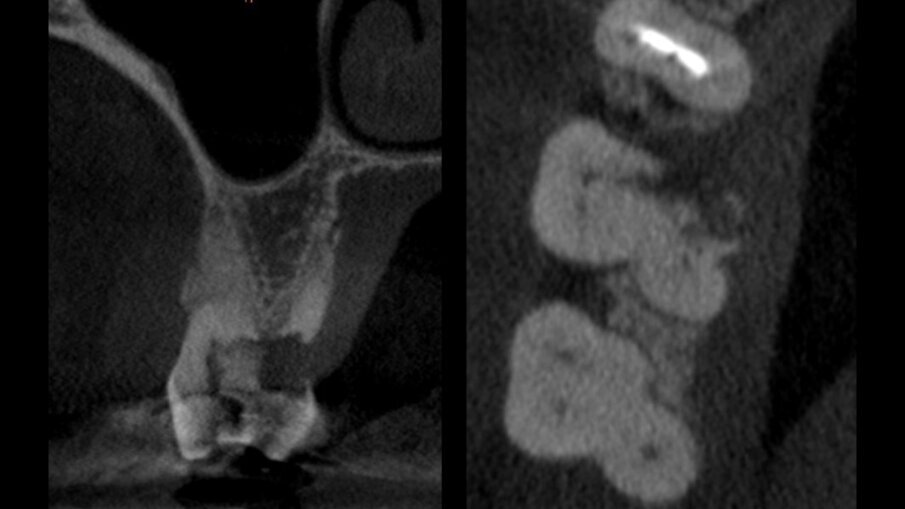

È stata eseguita una CBCT preoperatoria (Figg. 2a, 2b). La paziente, una donna di 52 anni in buona salute, ha iniziato la terapia antibiotica il giorno prima dell’estrazione con 2 gr. Amoxicillina e Acido Clavulanico. Dopo l’anestesia locale, è stata eseguita un’estrazione atraumatica cercando di non danneggiare le corticali ossee. L’alveolo è stato accuratamente pulito e risciacquato con acqua ossigenata e clorexidina 0,2% (Fig. 3). È stata praticata un’incisione intrasulculare sull’aspetto vestibolare dell’alveolo estrattivo, estendendosi al centro dei denti adiacenti. Un lembo a tutto spessore è stato sollevato ed il periostio staccato con micro-scollatori ha permesso di creare una busta per la lamina corticale (Fig. 4). La lamina corticale soft da 0,5 mm è stata prima idratata per cinque minuti in soluzione sterile e poi tagliata nella forma desiderata, tra 8 e 10 mm di altezza e con un’estensione che copre i margini mesiali e distali dell’alveolo estrattivo. La lamina corticale può essere facilmente inserita nel sito ed eventualmente ritagliata fino ad ottenerne un perfetto adattamento. I bordi devono essere rifiniti con angoli arrotondati per ridurre il rischio di perforazione e/o deiescenze sul versante vestibolare. La colla di fibrina umana (Tisseel, Baxter) è stata diluita al 10% mediante 0,9 ml di acqua bidistillata. Sulla lamina corticale sono state applicate due o tre gocce di colla, dopo di che la lamina è stata poi schiacciata con una gentile pressione digitale per adattarsi alla posizione predefinita (Fig. 5). Il lato palatale dell’alveolo è stato invece lasciato guarire per prima intenzione. Una spugna di collagene (Condress, Smith & Nephew) è stata inserita all’interno dell’alveolo per stabilizzare il coagulo ed è stata posizionata una sutura incrociata (4-0 punti di sutura in ptfe) per mantenere la spugna in posizione, le papille sono state invece suturate con due suture a fionda7 (Fig. 6). Quattro mesi dopo l’estrazione, prima di inserire l’impianto, è stata eseguita una CBCT post-operatoria per valutare la guarigione del sito operato.

Figg. 2a, 2b - CBCT pre-estrazione